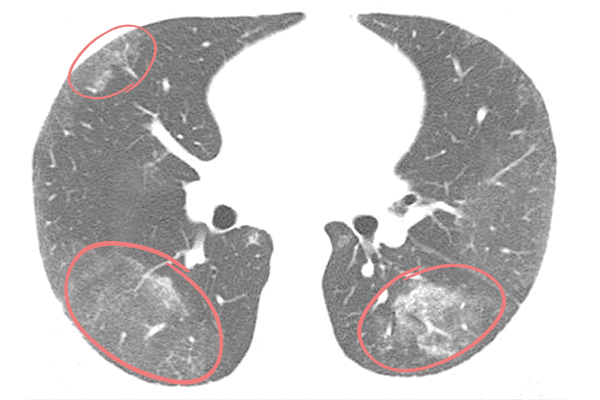

По данным актуальных исследований, публикуемых в журнале Radiology, вирусная пневмония, вызванная COVID-19, чаще всего проявляется на КТ изображениях в виде двухсторонних затемнений по типу «матового стекла» и уплотнений легочной ткани, например, утолщения альвеолярных перегородок. На томограммах это, напротив, более светлые участки, поскольку они свидетельствуют о повышенной плотности легочной ткани, а она хуже пропускает рентгеновские лучи.

Наличие одиночного очага поражения по типу «матового стекла» в правой нижней доле легкого может быть интерпретировано как начальное, самое первое проявление вирусной пневмонии.

Матовое стекло при коронавирусе

«Матовые стекла» считаются основным признаком поражения легких при пневмонии. Так называют участки легочной ткани, в которых альвеолы заполнены жидкостью — это инфильтраты. Название отсылает непосредственно к визуализации этого признака при лучевой диагностике. Уплотнения по типу «матового стекла» напоминают беловатый налет, легочная ткань — светлая.

«Матовые стекла» при коронавирусе обычно локализуются с обеих сторон (двусторонняя пневмония) в нижних и боковых отделах, ближе к плевре либо сконцентрированы вокруг бронхов. При этом сохраняется видимость сосудов, бронхов и их стенок. По количеству и размерам инфильтратов определяют степень поражения легких.